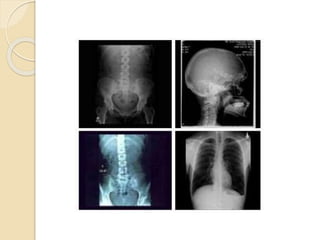

What is radiography ?

 Radiography is an imaging technique

that’s uses electromagnetic radiation

other then visible light.

 Specially x-ray

 It is use to view internal structure of

human body

What Is Digital Radiography?

What is radiography?  Radiography is an imaging technique that’s uses electromagnetic radiation other then visible light.  Specially x-ray  It is use to view internal structure of human body